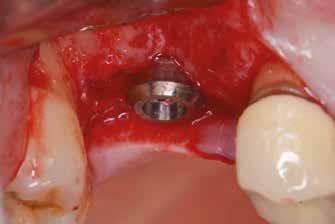

1. ábra: Műtét előtti fogászati panorámafelvétel, amelyen a hiányzó felső állcsont jobb első premolárisát és a szabad véggel rendelkező hidat láthatjuk. — 2. ábra: Az implantátum méreteinek megtervezése CBCT-vel. 3. ábra: Bukkális lágyrészdefektus. — 4. ábra: A biológiai szélesség értékelése a vertikális lágyszövetvastagság alapján. 5. ábra: Palatinális „tekercslebeny” – Palatal roll flap. — 6. ábra: Bredent medical copaSKY 4x10 implantátumbeültetés. 7. ábra: Szubkresztális implantátumbeültetés a várható biológiai szélességnek megfelelően.

8. ábra: Egyéni ínyformázó titánbázison, tulipán alakú emergenciaprofillal. — 9. a. ábra: A sebzárás okkluzális nézete.

(2. ábra). A lágyszövetek értékelése Seibert szerinti I. osztályú csontdefektust állapított meg (3. ábra), ezért a beavatkozáskor palatinális „tekercslebenyt” preparáltunk (palatal roll flap), és implantációt végeztünk, hogy kompenzálni tudjuk a bukkális lágyszövet-behúzódást. Megmértük a vertikális lágyszövetvastagságot, és úgy terveztük, hogy a szubkresztális implantátum beültetése összhangban legyen a biológiai szélesség kialakulásával a transzgingivális gyógyulási periódus alatt (4. ábra)

Sebészeti eljárás

Az eljárást helyi érzéstelenítés mellett végeztük (4%-os articaine-hidroklorid 1:100 000 adrenalinnal). Papillakímélő, U alakú palatális bemetszést végeztünk, teljes vastagságú nyálkahártyalebeny preparálás történt, a lebenyt bukkálisan feltekertük (5. ábra). A lebeny bukkálisan feltekert részén de-epitelizációt végeztük el, amellyel kompenzálni tudtuk a bukkális lágyszöveti defektust. Szakaszos előfúrást végeztünk, és a bredent copaSKY 4x10 implantátumot 30 Ncm behajtási nyomatékkal helyeztük be (6. ábra). Az implantátumot 1 mm-re szubkresztálisan helyeztük be, hogy később szélesebb emergenciaprofilt tudjunk kialakítani (7. ábra). Az egyedi ínyformázó úgy készült, hogy kompozitot vittünk fel a titánbázisra, és így formáztuk a lágyszöveteket a transzgingivális gyógyulási fázis során (8. ábra). Az egyéni ínyformázó tulipán formájú, hogy kialakítsa a kívánt emergenciaprofilt. A lágyszövetet feszülésmentesen zártuk #6/0 nem felszívódó, monofil fonallal (Optilene, B. Braun Deutschland; 9. a–b. ábra). Posztoperatív röntgenfelvétel készült, ami alapján az implantátum a szomszédos fogakkal párhuzamos elhelyezést mutatott (10. ábra). Posztoperatív utasításokat adtunk a páciensnek a műtéti terület körüli szájhigiénia fenntartása érdekében. A beavatkozást követő egy héttel a varratokat eltávolítottuk, és a kezelt terület kielégítő gyógyulást mutatott (11. ábra). A 4 hónap utáni késleltetett terhelést a páciens kívánsága szerint terveztük.